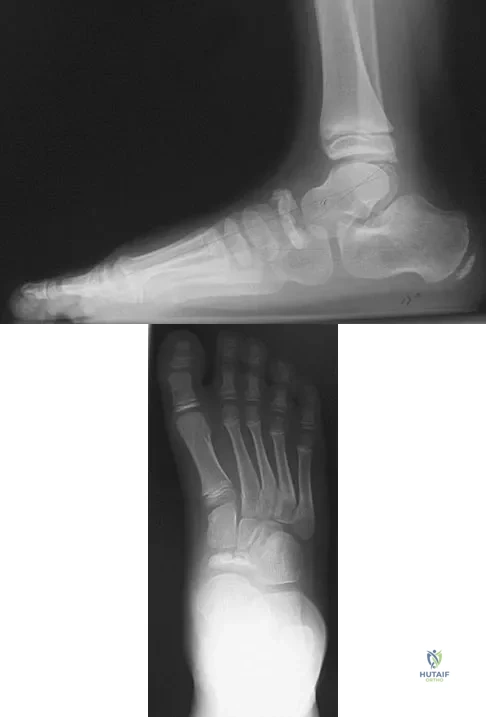

Figures 3a and 3b show the inversion stress radiographs of a patient's ankle. What is the most likely ligament injury pattern?

Explanation

A 19-year-old woman has had a painful prominence on the lateral border of her fifth metatarsal head since she was a young girl. Nonsurgical management, including the use of a wide toe box shoe, has failed to provide relief. Examination reveals a callus over the lateral prominence and on the plantar portion as well. A clinical photograph and a radiograph are shown in Figures 34a and 34b. Treatment should consist of

Explanation

A 69-year-old man reports pain over his bunion while wearing shoes and pain in the joint with push-off when barefoot. Nonsurgical management has failed to provide relief. Radiographs are shown in Figures 8a and 8b. What is the surgical procedure of choice?

Explanation